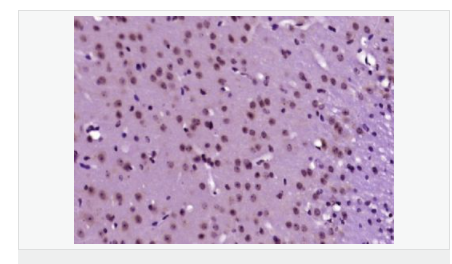

| 產品應用 | WB=1:500-2000 ELISA=1:5000-10000 IHC-P=1:100-500 IHC-F=1:100-500 ICC=1:100-500 IF=1:100-500 (石蠟切片需做抗原修復) not yet tested in other applications. optimal dilutions/concentrations should be determined by the end user. |

| 細胞定位 | 細胞核 細胞漿 |